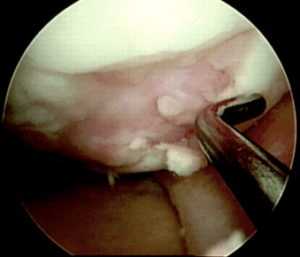

РИСУНОК 9. Аккуратная импакция остеохондрального трансплантата в подготовленный для него канал с помощью импактора, размер которого на 1 мм превышает размер самой пробки. (А) Артроскопическая картина. (Б) Схема. РИСУНОК 10. Пример успешно выполненной остеохондропластики хондрального дефекта мыщелка бедра. (А) Интраоперационная картина сразу по завершении остеохондропластики. (Б) Признаки интеграции трансплантата при повторной артроскопии. РИСУНОК 11. Крупные дефекты могут потребовать использования нескольких остеохондральных трансплантатов или т.н. пластики в форме «снеговика», при этом каждое последующее реципиентное ложе должно формироваться только после завершения имплантации остеохондральной пробки в предыдущее ложе.